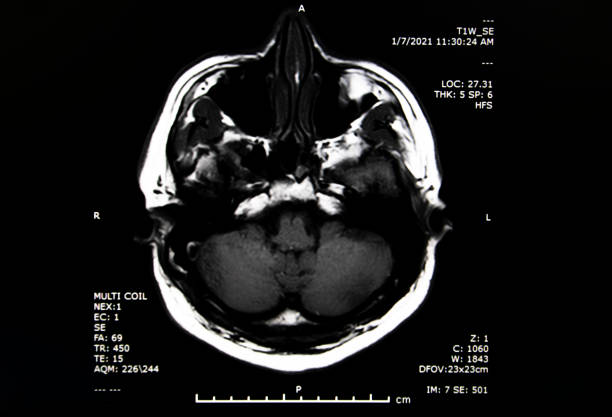

4. 뇌관 부위 손상

뇌관은 우리 몸의 생체 징후를 담당하는 부위로, 이상이 있는 경우 음식을 적절히 소화하지 못하게 되어 식사에 어려움을 겪을 수 있습니다. 호흡 장애도 발생할 수 있어 인공호흡 장치가 필요할 수 있습니다.